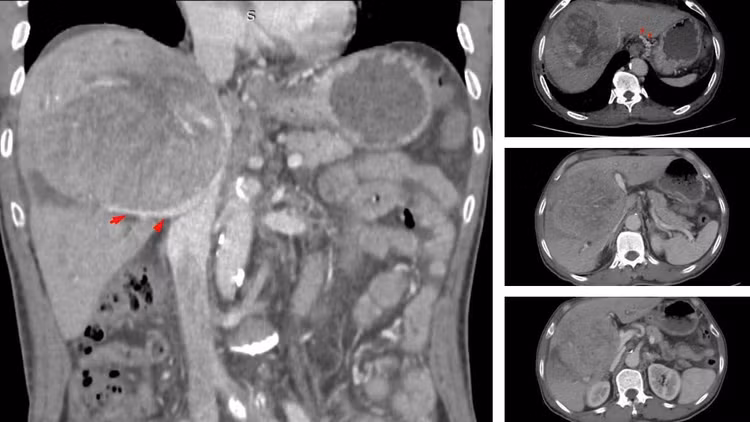

Khi kiểm tra, kết quả khối u gan đã đạt kích thước khổng lồ 10–12 cm. Tại một số cơ sở y tế, ông từng nhận được tiên lượng thời gian sống còn lại có thể không quá 9 tháng.

Khối u gan kích thước khổng lồ và người bệnh được chẩn đoán ung thư gan giai đoạn muộn - Ảnh BVCC

Theo BSCKII Nguyễn Trường Giang, Phó Giám đốc Trung tâm Phẫu thuật Gan mật - Tiêu hóa, ngay khi tiếp nhận, đây đã là một ca bệnh rất nặng. Khối u khổng lồ chiếm gần hết nhu mô gan, chèn ép rốn gan và tĩnh mạch, gây ra tình trạng cổ chướng nhẹ và phù hai chân.